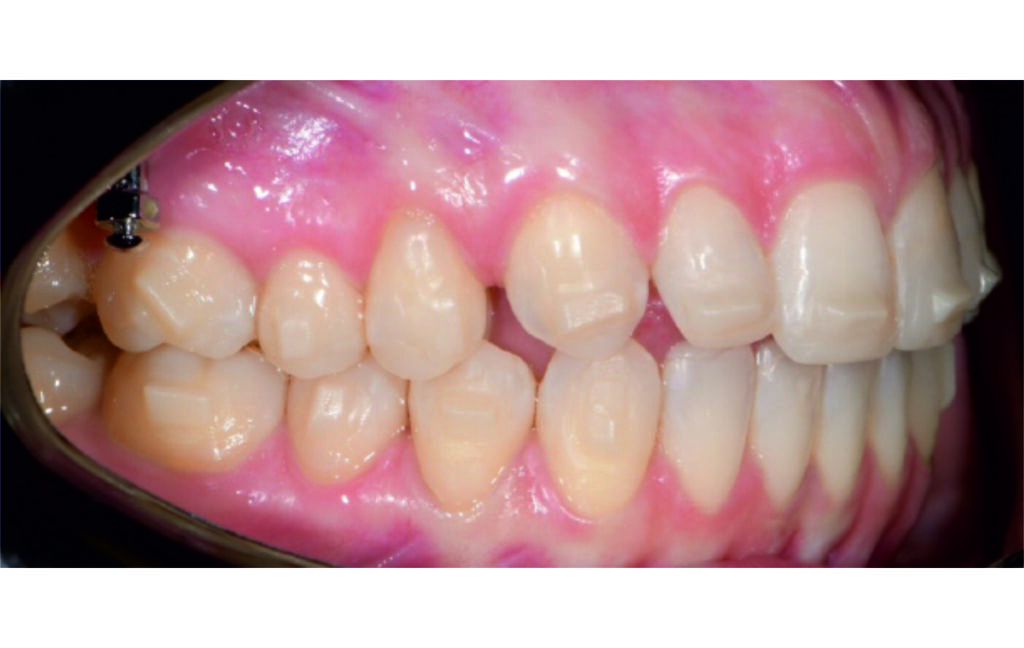

Malocclusion Class II on both sides due to mesial rotation of 16 26

Angle Class II 2mm on the right, Angle Class II 2mm on the left, light mandibular asymmetry to the right, lower central line 1mm to the right, upper central line 1,5mm to the left, 1mm overjet and overbite. Sagittal asymmetry of upper dental arch. Light crowding upper and lower frontal segments, severe attrition of posterior teeth, night bruxism. Normal sagittal position of both jaws, high angle case, steep mandibular ramus,excessive lower facial height, open bite tendency.

The case initially presented as a moderate Class II on the right and a Class II tendency on the left, with tapered dental arches and an anterior open bite extending to tooth 26 in segment II.

A 1.5 mm deviation of the upper dental midline to the patient’s left was noted, along with a slight mandibular midline shift to the right, likely due to asymmetrical mandibular growth observed in the facial structure. Severe mesial rotations of teeth 16 and 26 were evident in the initial records. As derotation of 16, 26, 17, and 27 progressed up to aligner 16, the premolars in segments I and II moved distally, resulting in a bilateral Class I relationship, as intended in the initial treatment plan.